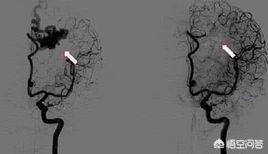

1.DSA

(インターベンショナル・アンギオグラフィー)

この検査は小手術に相当し、入院が必要である。医師は患者の血管に造影剤を注入し、X線装置の助けを借りて血管内の病変-梗塞、狭窄、動脈瘤、血管奇形など-をはっきりと見ることができる。この検査には数千ドル以上の費用がかかる。

DSA技術で血管内病変を発見

3.冠動脈造影:

冠動脈造影は主に冠状動脈性心臓病の診断を確認するために使用されます。

DSA(インターベンショナル・アンギオグラフィ)は約5,000ドル。